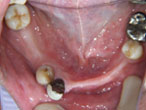

初診時

上下顎に数本の歯が残っていますが咬合支持がほとんどないために満足に食事もできない状態でした。また、下顎前歯部から臼歯部にかけて骨吸収が進行しており、上顎臼歯部にインプラント治療を行うためには骨造成が必要な状態です。

下顎